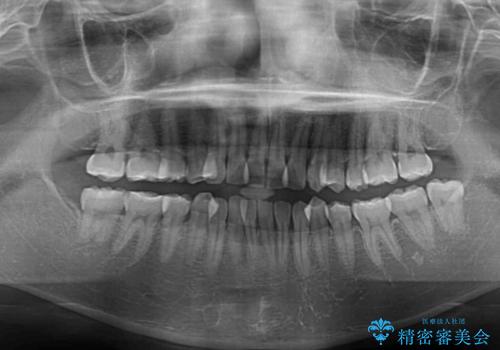

- 上下前歯のデコボコを気にして来院された患者様です。

上顎歯列が下顎の歯列に対して狭小であり、一部下顎の奥歯が上顎よりも外側に位置している状態でした。

上顎の急速拡大装置を使用して上顎骨を側方に拡大することで上顎歯列を拡大し、下顎歯列も拡大できるようにすることで、歯列を整えることとしました。